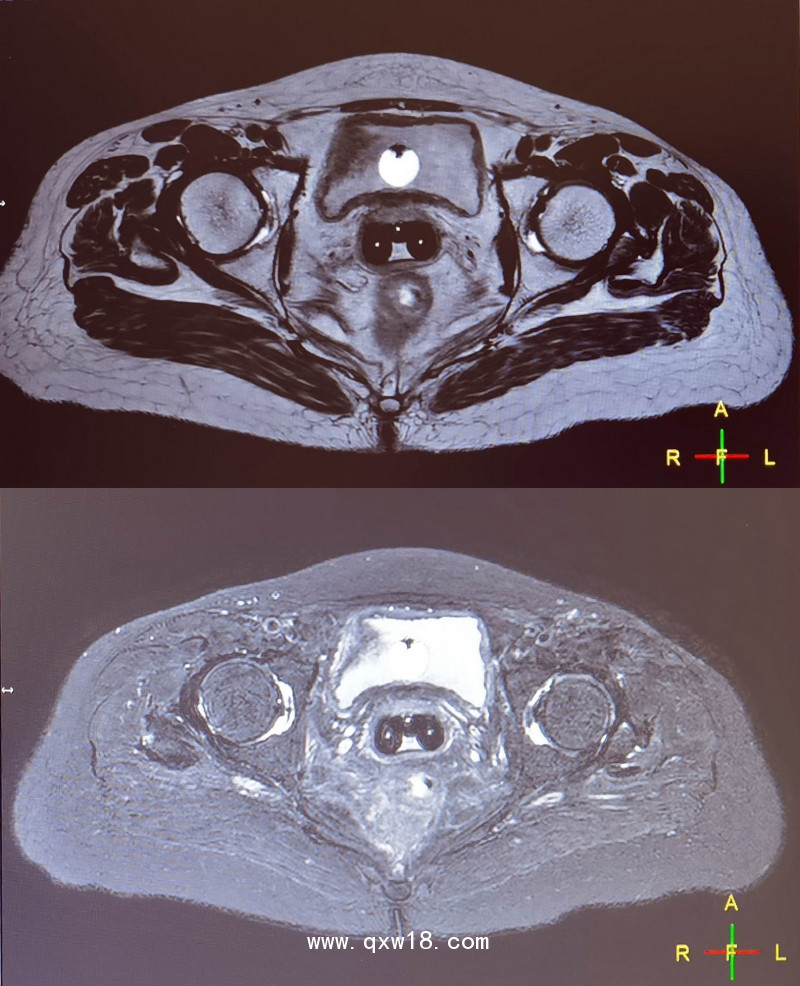

三維后裝CT/MR施源器&插植針MR成像標(biāo)記線作為三維后裝施源器中的組件,能在MR定位時(shí)T2WI、T1WI中突顯,是治療計(jì)劃制定和放療實(shí)施理想的定位標(biāo)記。

產(chǎn)品優(yōu)點(diǎn):標(biāo)記線橫斷MR掃描在T2WI、T1WI、STIR、FLAIR序列上均呈明顯的高信號(hào)標(biāo)記。